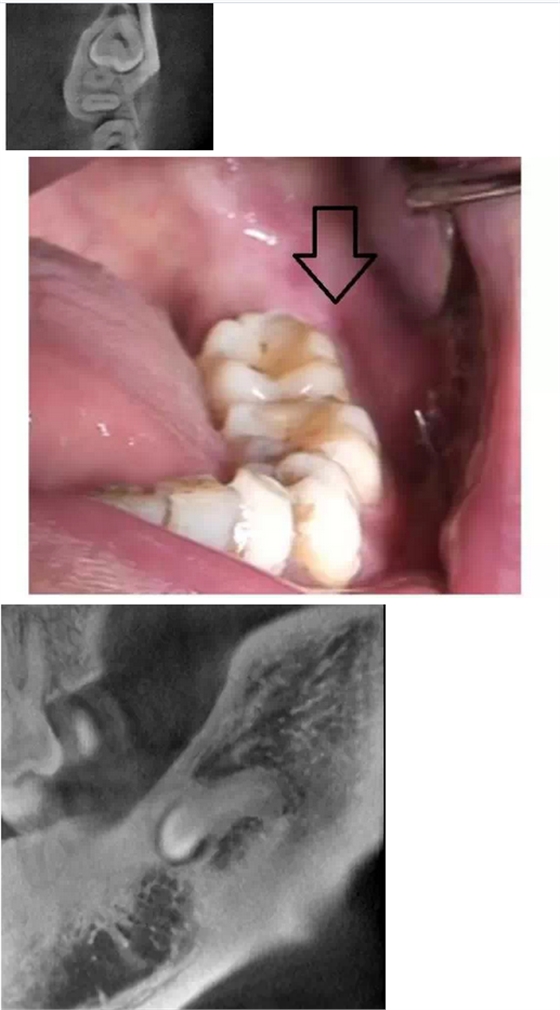

在拔牙一月后,鳥槍換大炮,診所引進了三維CT,左側(cè)智齒在拍了CT后,前后頰舌上下關(guān)系就一目了然,此牙更難拔除,因為完全埋伏(圖二),其上面覆蓋有3mm厚的牙槽骨,其下緣與下牙槽神經(jīng)管緊緊相連,較危險;牙冠前緣與第二磨牙遠中根也緊緊相連,后緣牙根向上翹;整個牙齒偏頰側(cè),頰側(cè)皮質(zhì)骨板較厚(圖三),舌側(cè)骨板也較厚,測好牙冠頸部上下距離約為9.5mm。

我們掌握了全方位的信息后,藉著CT向患者講解該牙齒的情況,患者充分理解拔牙的風(fēng)險和醫(yī)生所需要的經(jīng)驗和勇氣。因著有CT,術(shù)前的準備更加充分:手術(shù)切口的設(shè)計和種植機去骨的部位選擇均在第二磨牙的遠中頰側(cè)(圖四);車針長度的定位在9mm,防止磨到神經(jīng)管;掌握了牙根根尖部分是彎向下(圖五),就可以評估常規(guī)的挺子是很難進去的,特別設(shè)計了四把不同角度的挺子。整個拔牙過程非常順利,行云流水,均在我們的掌握之中,猶如四驅(qū)的牧馬,人雖行駛在惡劣的沙漠地,仍是馳騁疆場,酣暢淋漓。

第二顆智齒在CT的輔助下整個拔除時間比第一顆減少了一小時,而且創(chuàng)口?。▓D六),術(shù)后反應(yīng)輕,患者在拔除的第二天胸悶的感覺就慢慢消失。